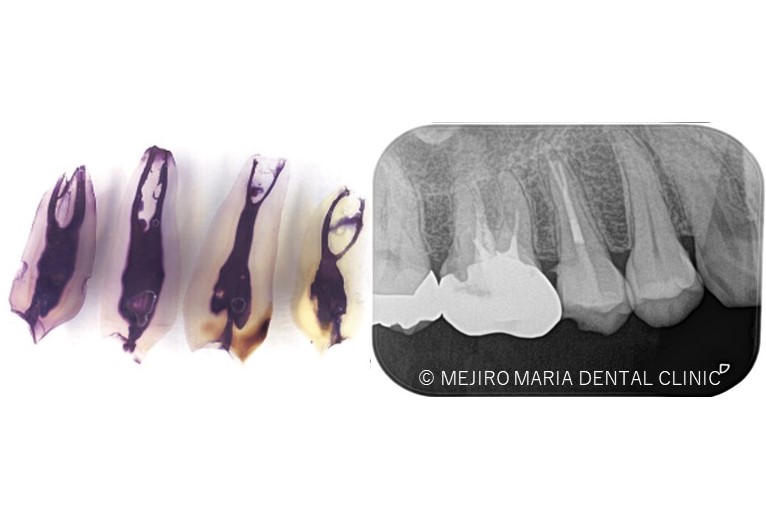

診査の結果、右上5番の歯髄には歯髄生活反応は確認できず、歯髄壊死が起因となる根尖性歯周炎と診断しました。術前のレントゲン診査により、根尖が2つに分岐していることを確認できます。

*赤丸で示しているところは、根が分岐している箇所を示す

今回は右上5番に対しての根管治療における、根尖3mmで分岐する根管へのアプローチでした。

当院のホームページでも記載があるように、根尖3mmは非常に複雑な形態をしていることから、根管治療でのアプローチの限界があるのも事実です。